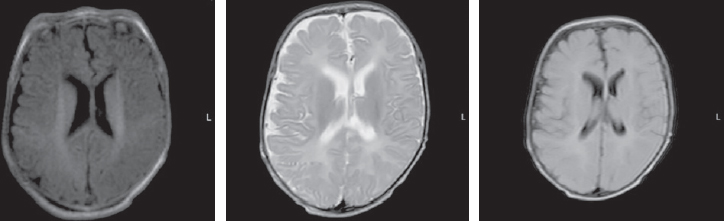

The child’s condition remained critical, with impaired consciousness, extension contractures in the elbow and knee joints, and non-epileptic paroxysmal states, such as bronchospasm and apnea persisting. Startle reflexes were pronounced and with any tactile stimulation, startle (generalized myoclonus) was registered. With the progression of neurological disorders, an increase in the cystic-atrophic changes was noted and hydrocephalus was formed. The data of MRI over a time, performed at the age of four months, are presented in Fig. 3.

Fig. 3. Magnetic resonance imaging of a patient at the age of 4 months. Axial sections, T1 VI, T2 VI, Flair. There is a negative dynamics in the form of cystic-atrophic changes in the large hemispheres of the brain with the formation of atrophic hydrocephalus. The appearance of symmetrical subshell clusters in the form of subdural hygromas

Рис. 3. Магнитно-резонансная томограмма пациента в возрасте 4 мес. Аксиальные срезы, Т1ВИ, Т2 ВИ, Flair. Наблюдается отрицательная динамика в виде кистозно-атрофических изменений в больших полушариях головного мозга с формированием атрофической гидроцефалии. Появление симметричных подоболочечных скоплений в виде субдуральных гигром

The MRI, performed at seven months of child’s age, revealed a moderate increase in the severity of atrophic changes. Bilateral cystic encephalomalacia of the cerebral hemispheres as well as atrophic hydrocephalus with dilatation of the external and internal cerebrospinal fluid spaces occured. Bilateral chronic subdural hematomas (hygromas) progressed (Fig. 4).

Fig. 4. Magnetic resonance imaging of a patient at the age of 7 months. Axial sections, T1 VI, T2 VI, Flair. There is a bilateral cystic encephalomalacia of the large hemispheres of the brain, atrophic expansion of the external and internal liquor spaces – a moderate increase in the severity of changes. Bilateral chronic subdural hematomas (hygromas) – a moderate increase in fluid volume

Рис. 4. Магнитно-резонансная томограмма пациента в возрасте 7 мес. Аксиальные срезы, Т1ВИ, Т2 ВИ, Flair. Отмечается билатеральная кистозная энцефаломаляция больших полушарий головного мозга, атрофическое расширение наружных и внутренних ликворных пространства — умеренное нарастание степени выраженности изменений. Двусторонние хронические субдуральные гематомы (гигромы) — умеренное увеличение объема жидкости